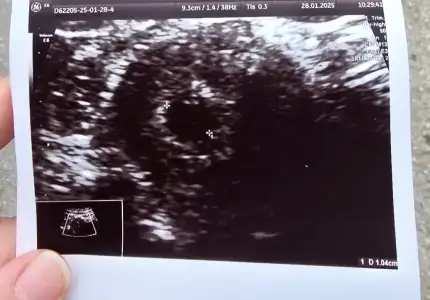

Muhtemel doğum tarihi 3.10.2025

Keseyi 4+6da gördük minicik de olsa